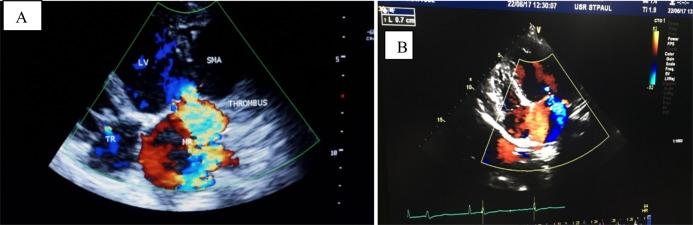

METHODS

In April 2017, a 25-year-old patient havingsubmitral left ventricular aneurysm with New York Heart Association (NYHA) class IV heart failure and mild left ventricular systolic dysfunctionreceived medical treatment at our institution. She had severe mitral regurgitation and aneurysmal thrombus. The diagnosis was easily made using GE Vivid E9 transthoracic echocardiography. She was given drugs for management of heart failure and anticoagulation.

RESULTS

Our patient was discharged with a stable condition, and she had no early mortality. At 3 months' follow-up,shehad clinical improvement with NYHA class II heart failure, slight improvement of left ventricular systolic function, and resolution of the left ventricular thrombus. However, there waspersistent severe mitral regurgitation and aneurysm.